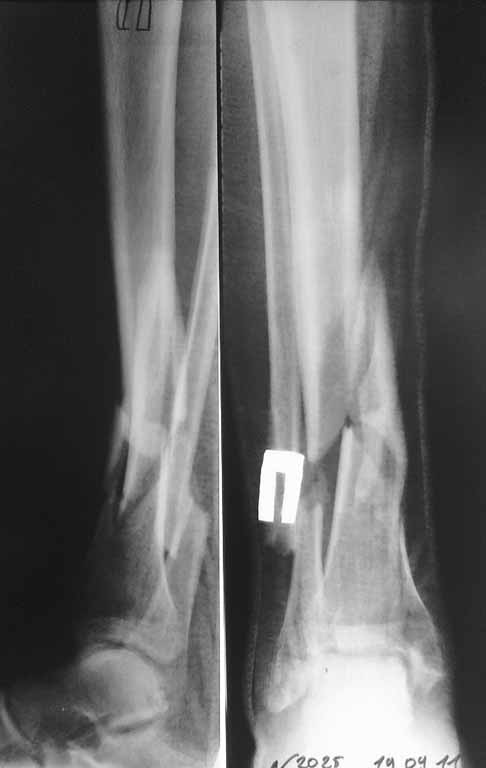

Я бы порекомендовал, если кожные покровы голени позволяют- произвести остеосинтез пластинами через общий передне-наружный доступ. И в первую очередь зафиксировать полутрубчатой 4,5мм или компрессионной 3,5мм пластиной АО перелом н/3 малоберцовой кости, чтобы стабилизировать отломки б/берцовой по длине.

Если с кожей не то- попытаться получить репозицию под ЭОП-ом и наложить аппарат АО до голеностопного сустава (собирать Илизаров - долго, нудно, да и, наверное нет необходимости...)

Уважаемый Сергей! Следует уточнить(для уважаемого сообщества) , что переломы находятся на разных конечностях, поэтому восстановление длины бедра потребует равнозначной коррекции длины голени. Либо, как предлагает профессор Djoldas Kuldjanov, не добиваться полной репозиции и пожертвовать частью дистального отломка, сохранив ось и ротацию. Корригировать длину голени проще ввиду меньших усилий по преодолению ретракции мягких тканей. Хотя пациент молодой и желательно наиболее полно восстановить конечности. Несомненно,аппарат Илизарова собирать долго и нудно и неохота, но возможность управляемой фиксации при минимальных экономических затратах перевешивает данные "недостатки". Да и не располагаем АО фиксаторами, гексаподами. Следует учесть и то , что при одномоментной коррекции длины голени (3,5 - 4 см) могут возникнуть трудности с зашиванием и заживлением операционных доступов. Еще позволю уточнить, что клинических признаков консолидации на голени нет - подвижность полная, что не потребует остеотомии малоберцовой кости. Поэтому желаю Вам, Сергей, удачи в одномоментной коррекции деформации бедра и остеосинтезе, но нужно быть готовым к варианту Александра Николаевича - дистрактор, дозированная коррекция смещения по длине, остеосинтез.